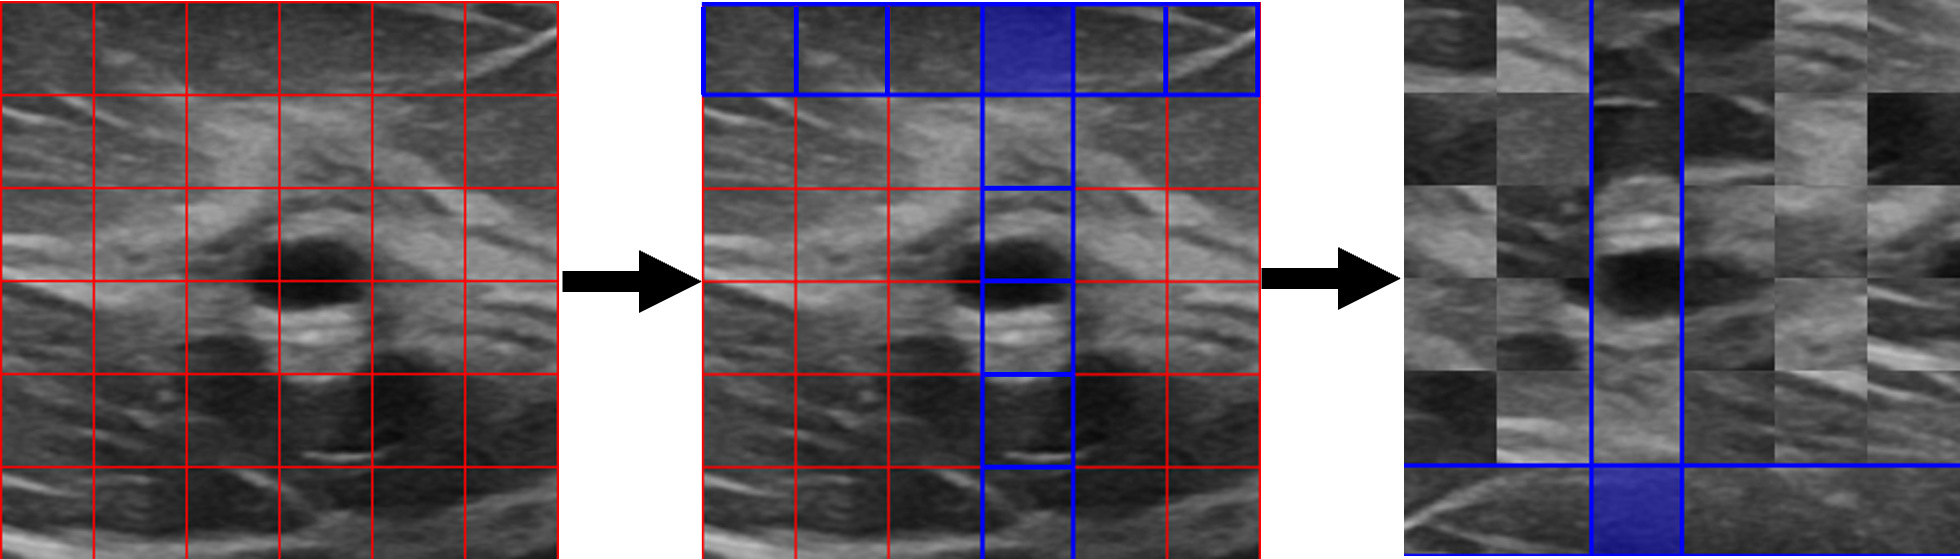

A frequency-augmented random cropped area of the image (see III-A1) is divided into 36 patches (Fig.3). We select a random patch from these patches (shown in filled blue in Fig. 3), say , where is the patch located at row and column . These are then used to determine two sets of patches, namely focal patches and non-focal patches . represents patches in the same row and column as the random initial patch (outlined in blue in Fig. 3).

| (4) |

are the complement of focal patches (outlined in red in Fig. 3).

| (5) |

All non-focal patches are shuffled (). Focal patches undergo horizontal and vertical flips before each patch is rotated to ensure visual coherence between focal patches.

| (6) |

This spatial operation provides a strong transformation to non-focal patches while weaker augmentation to the focal patches. This operation maintains partial layer-wise structure information within the image. In Fig. 1, .